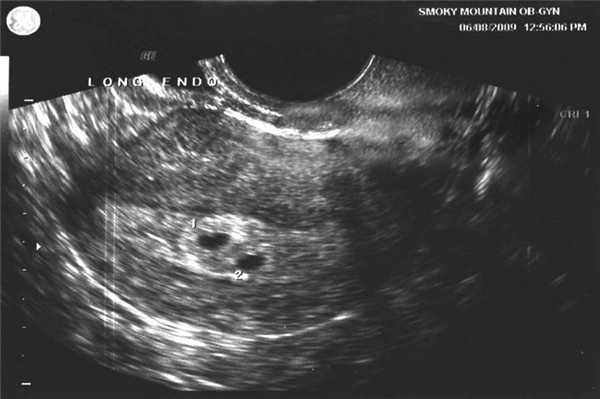

Фото УЗИ ребенка на разных сроках беременности

Если беременность желанная, будущие родители внимательно относятся к пренатальной диагностике плода. Чтобы убедится, что ребенок развивается нормально, в течение 9 месяцев гинеколог несколько раз направляет женщину на ультразвуковое исследование. Фото УЗИ может многое рассказать врачу и будущим родителям о малыше. Кроме того, снимок станет трогательным напоминанием для семейного архива.

Снимок УЗИ плода на 3 неделе

3 акушерская неделя соответствует 1 эмбриональной. Это значит, что на этом этапе происходит оплодотворение яйцеклетки и имплантация эмбриона в стенку матки. Проводить ультразвуковое исследование на столь раннем сроке не имеет смысла, поскольку даже самые современные датчики с высоким разрешением не показывают плод. Назначают процедуру только, если есть подозрение на внематочную беременность.

Ультразвуковое исследование на 4 неделе

На этом этапе формируется эмбрион. Его размеры еще сравнимы с размерами макового зернышка, а вес не превышает 0,5 грамм. УЗИ проводится для подтверждения зачатия и определения места прикрепления эмбриона. На снимке врач видит небольшую точку на поверхности эндометрия матки.

Фото УЗИ ребенка на 5 неделе беременности

В это время плод представляет собой нервную трубку с зачатком головного мозга. Клетки активно делятся, закладывается нервная и дыхательная системы. Размер плода в длину составляет около 1,5 мм, а вес не превышает 1 грамма. УЗИ подтверждает зачатие и имплантацию эмбриона в матке, но не позволяет выявить какие-либо патологии.

Данные ультразвука на 6 неделе

Плод активно растет. У него исчезает хвостик, формируется костная ткань, образуются нос и глаза. Ультразвуковое исследование обычно проводят при помощи внутривлагалищного датчика. Врач может услышать сердцебиение плода, а на фото отчетливо видно место прикрепления плодного яйца. Если беременность многоплодная, это видно на снимке. Также можно с высокой точностью определить дату зачатия.